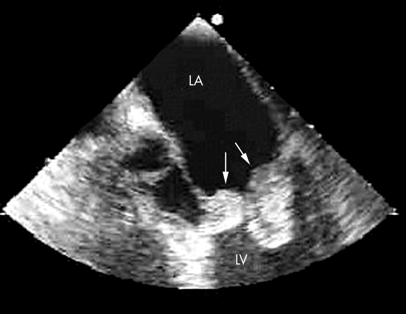

- Ecocardiograma: El ecocardiograma es una herramienta fundamental para el diagnóstico de la endocarditis. Puede ser de dos tipos:

- Ecocardiograma transtorácico (ETT): Utiliza ondas de sonido para crear imágenes del corazón desde el exterior del cuerpo, es un ultrasonido del corazón. Puede mostrar vegetaciones (acumulaciones de bacterias y tejido) en las válvulas cardíacas.

- Ecocardiograma transesofágico (ETE): Se realiza introduciendo una sonda a través del esófago para obtener imágenes más detalladas del corazón. Es especialmente útil para detectar vegetaciones pequeñas en las válvulas cardíacas.

- Evidencia de endocarditis en ecocardiograma:

- Vegetaciones detectadas en el ecocardiograma transtorácico o transesofágico, o abscesos intracardíacos.